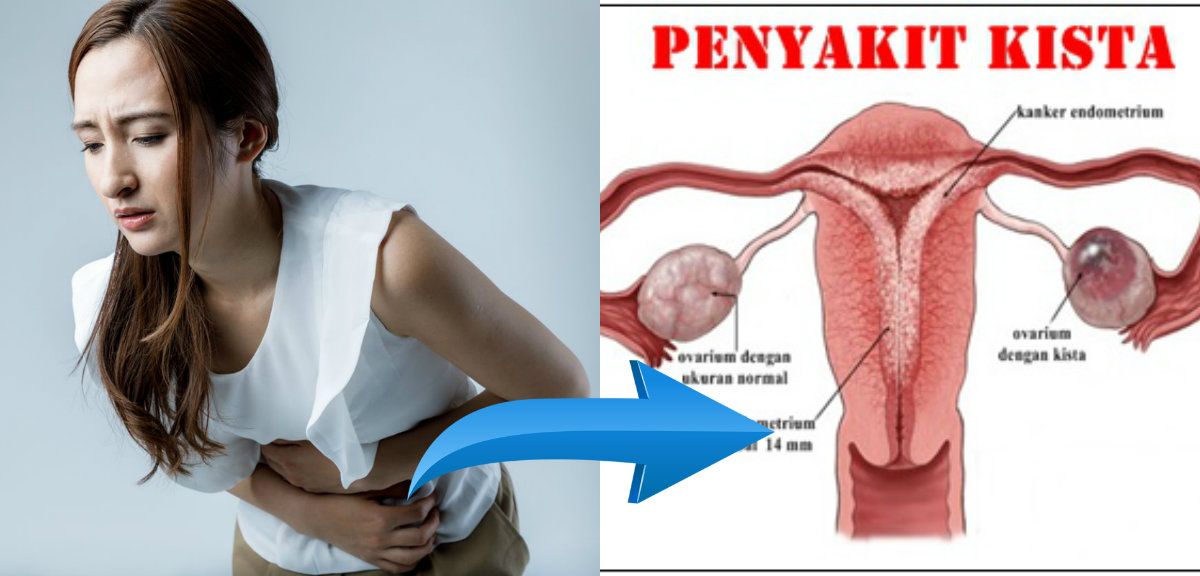

9 Macam Kista yang Harus Kamu Waspadai Sebelum Telanjur Parah

9 Macam Kista yang Harus Kamu Waspadai Sebelum Telanjur Parah